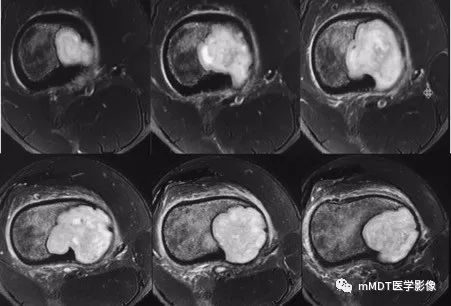

MRI横断面T2WI脂肪抑制序列

CT见病变位于股骨远端干骺端,呈分叶状、偏心膨胀性生长,密度欠均匀,整体低于肌肉密度,部分区域密度接近水,其内可见点状、线状、弧形、圆形的高密度影,大部分边缘硬化,局部深侵蚀骨内膜,局部骨壳不完整。MR上,T1WI信号略低于肌肉,T2压脂呈现不均匀高信号,未见明确软骨小叶结构及纤维分隔,周围可见水肿。